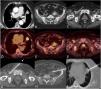

(A) Axial CT image (lung window) shows a suspicious lung nodule in the left upper lobe (asterisk). (B and C) Axial CT images show an ill-defined left retroperitoneal mass (B, asterisk) and an enlarged right lymph node (C, arrow). (D–F) Axial fused PET/CT images corresponding to lesions shown in A–C, respectively, show intense FDG uptake by the left upper lobe lung nodule but mild FDG avidity by the retroperitoneal lesion and inguinal lymph node. (G–I) Axial CT images show the needles targeting the enlarged right inguinal lymph node (G), the left retroperitoneal lesion (H), and the left upper lobe nodule (I), respectively. The duration of the triple lung biopsy procedure was 54min (time elapsed between the acquisition of the first CT scout and the last series acquisition), and the patient was discharged 6h following the procedure.

A 74-year-old active smoker female was found to have a suspicious lung nodule in the left upper lobe (Fig. 1A). An 18F-fluorodeoxyglucose (FDG) whole-body positron emission tomography/CT (PET/CT) performed for staging purposes ruled out mediastinal involvement but detected two additional extrathoracic lesions: a left retroperitoneal mass (Fig. 1B) and an enlarged right inguinal lymph node (Fig. 1C). PET/CT also confirmed that the FDG-avidity of the lung lesion (maximum standardized uptake value [SUVmax]: 9.8) was significantly different than that of the extrapulmonary lesions (SUVmax of retroperitoneal mass: 5.7; SUVmax of inguinal lymph node: 5.2), suggesting the possibility that the three lesions could represent different conditions (Fig. 1D–F). Since the patient was taking apixaban for atrial fibrillation, the interventional thoracic radiologist proposed to attempt a triple CT-guided core-needle biopsy during one single session. The uneventful triple CT-guided core-needle biopsy procedure was performed sequentially: first, the lesion with the lowest anticipated biopsy-related risk (the inguinal lymph node) was biopsied (Fig. 1G); second, the lesion with an intermediate biopsy-related risk (the retroperitoneal mass) was biopsied (Fig. 1H); and last, the lesion with the highest biopsy-related risk (the lung nodule) was biopsied (Fig. 1I). The pathological diagnosis confirmed that the pulmonary lesion was a primary lung adenocarcinoma (stage I) whereas the other 2 lesions represented a non-Hodgkin's lymphoma. The patient was treated first for her lung cancer (thoracoscopic surgery) and 1 month later she initiated systemic chemo-immunotherapy for the non-Hodgkin's lymphoma.